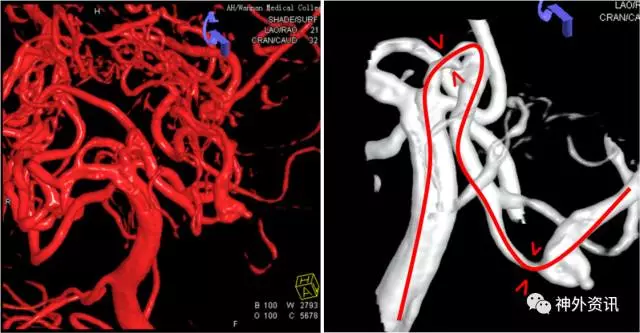

(脑动脉CTA:前交通动脉瘤+右侧额叶AVM)

(右侧额叶AVM:双侧大脑前动脉+右侧大脑中动脉供血,静脉引流入矢状窦)

(左侧颈内动脉优势供血前交通微小动脉瘤2枚)

(治疗计划:支架辅助弹簧圈栓塞2枚前交通动脉瘤)

(Envoa DA导引导管—左侧颈内动脉海绵窦段)

(瘤1:单纯弹簧圈栓塞致密,动脉瘤不显影)

(瘤2:支架辅助弹簧圈栓塞致密,动脉瘤不显影)

(术后3D双容积重建和Dyna CTA)